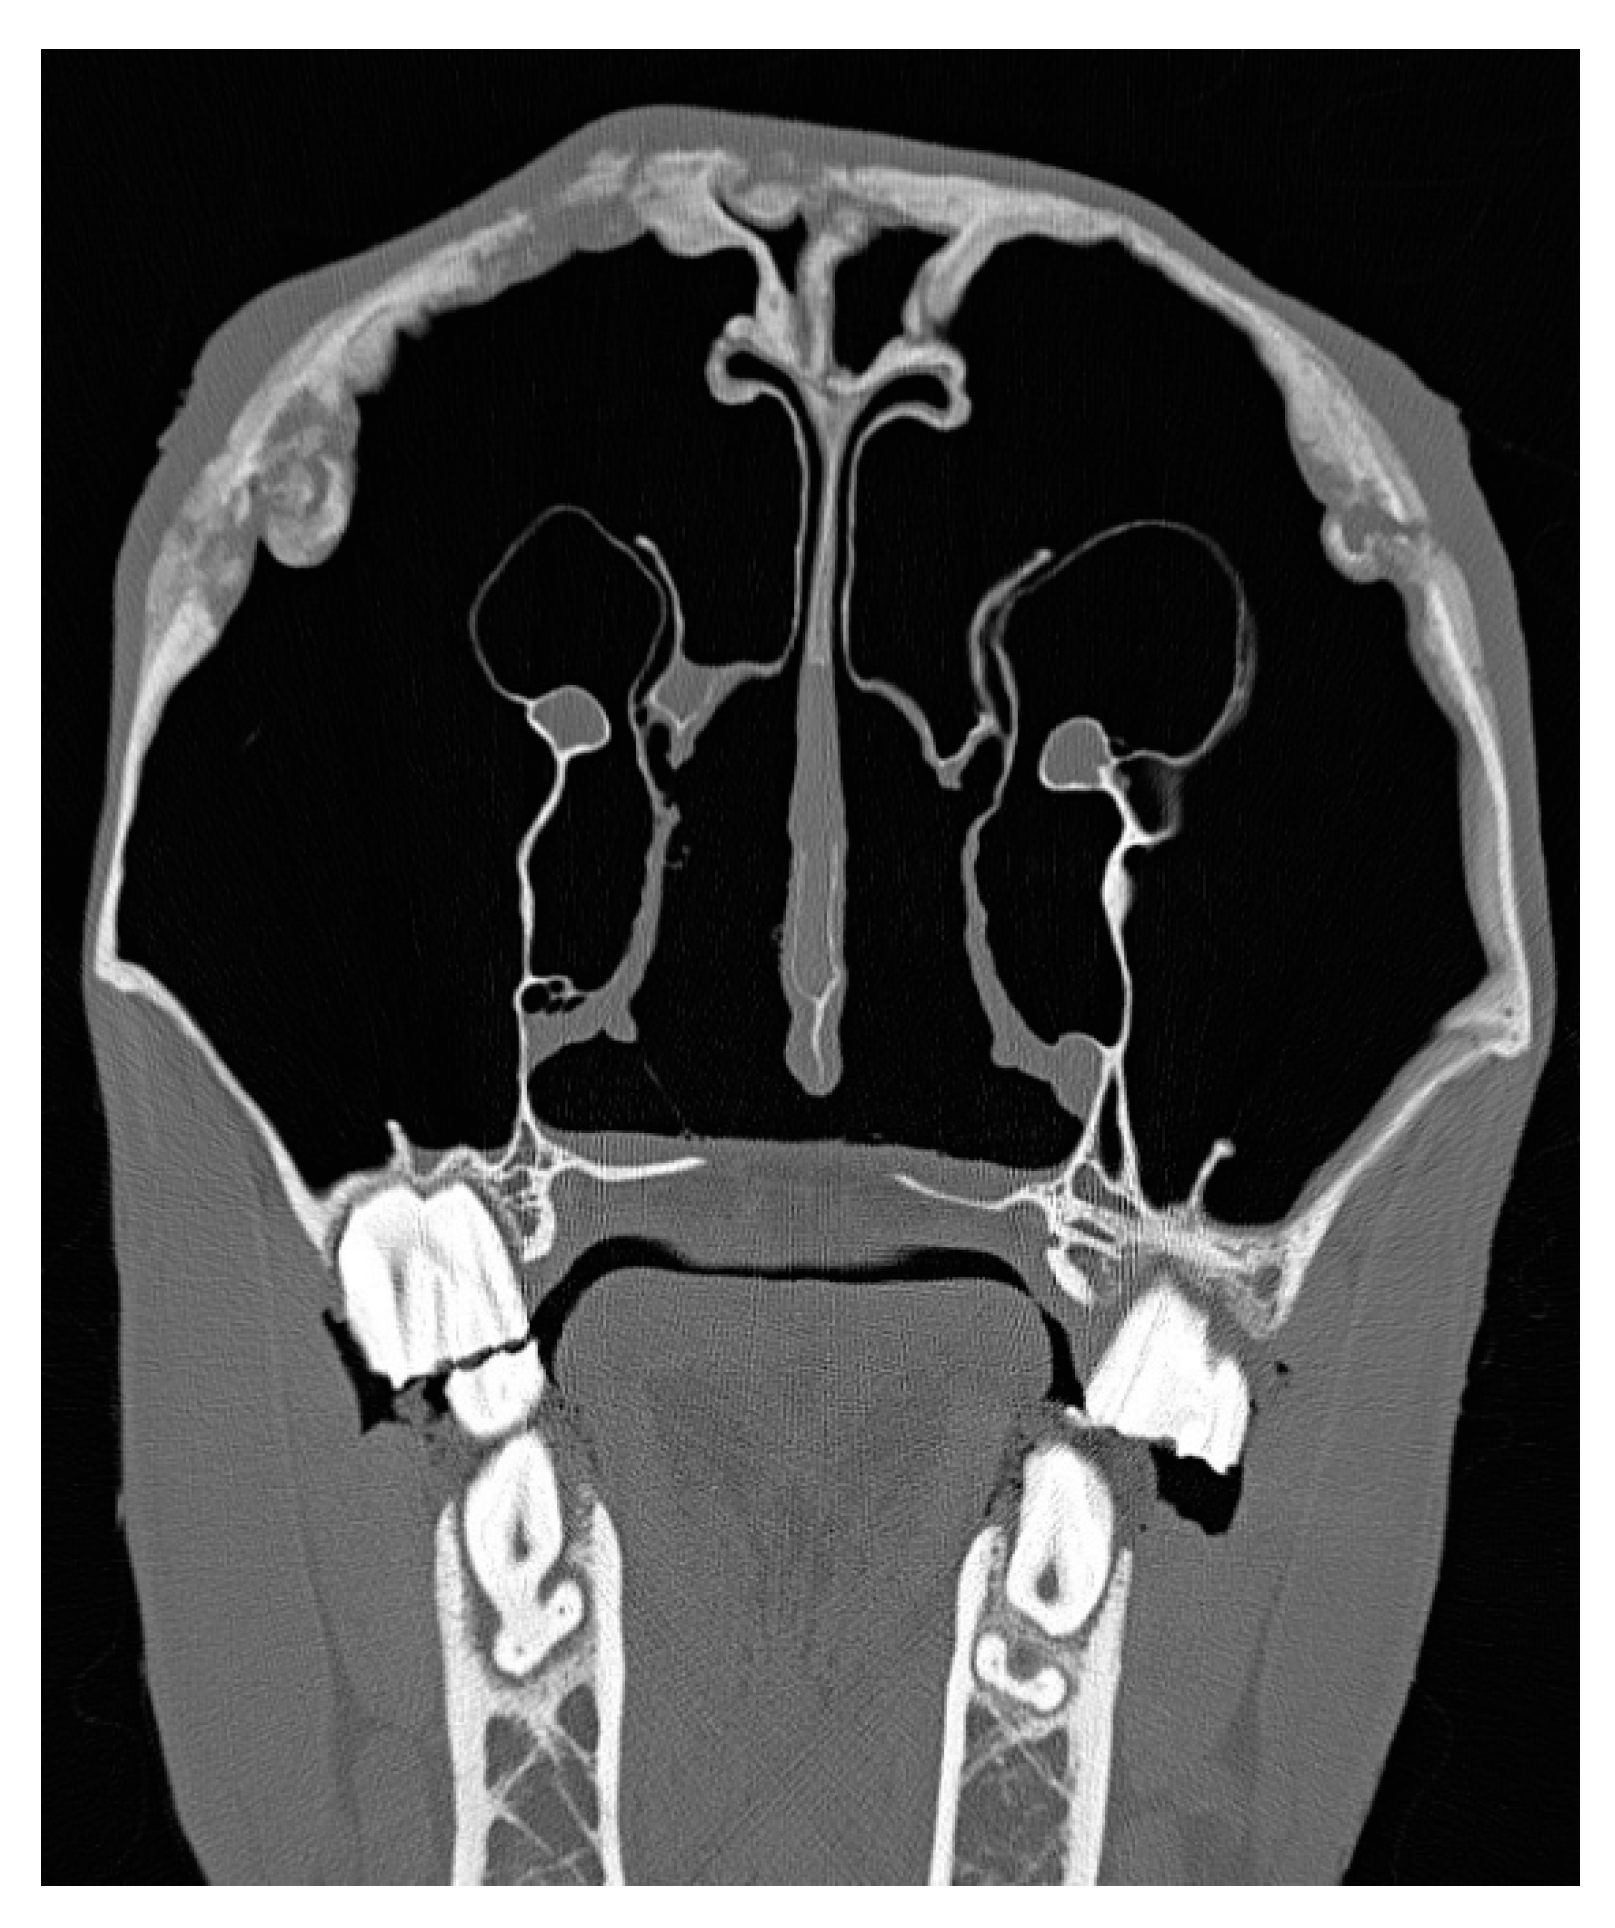

3.2. Imaging Findings